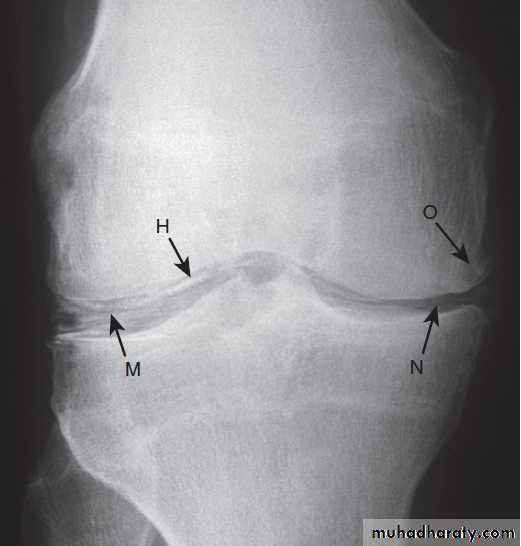

Pathological changes in osteoarthritis.

A Abnormalnests of proliferating chondrocytes (arrows) interspersed with matrix devoid

of normal chondrocytes.

B Fibrillation of cartilage in OA.

C Radiograph

of knee joint affected by OA, showing osteophytes at joint margin (white arrows), subchondral sclerosis (black arrows) and subchondral cyst (open arrow).

X-ray appearances in knee osteoarthritis. There is almost complete loss of joint space affecting both compartments,

And sclerosis of subchondral bone.

X-ray of hip showing changes of osteoarthritis. Note

the superior joint space narrowing (N), subchondral sclerosis (S), marginalosteophytes (white arrows) and cysts (C).